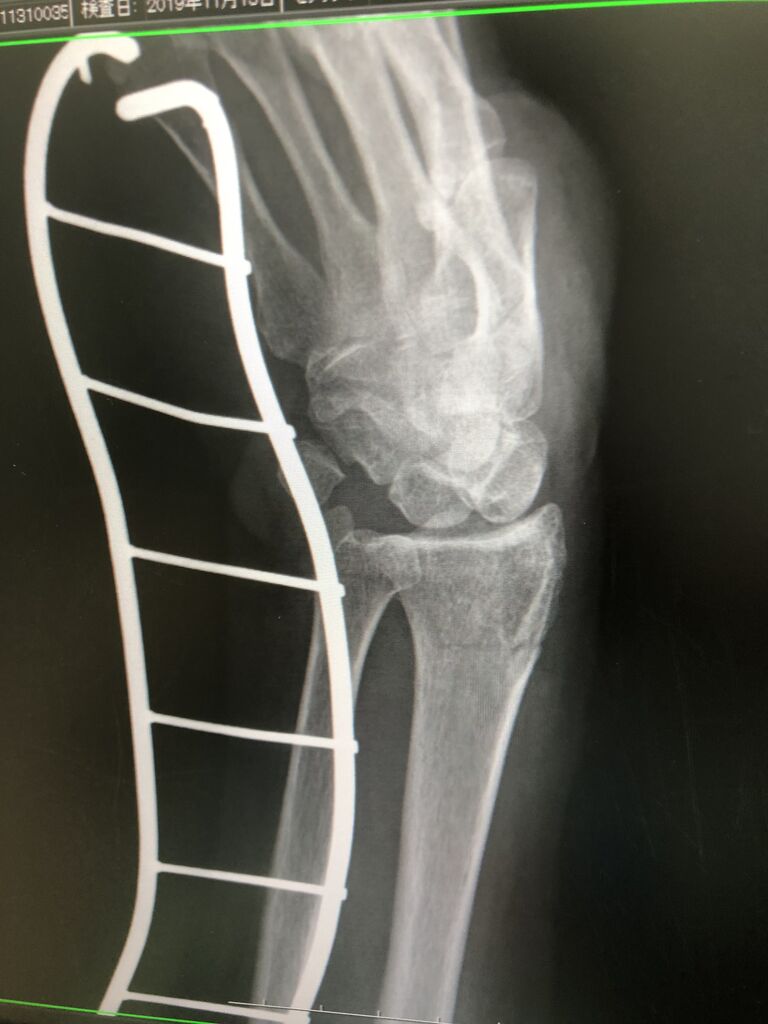

前十字靱帯は

アスリートで、よくおこる

膝外傷です。

切れると 1年を棒にふってしまいますが、

当院でも、年間40人ぐらい、

前十字靭帯断裂のアスリートがこられますが、

モチベーションを前むきにして、手術施設と

連携して、復帰していきます!